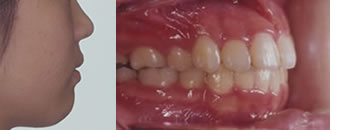

■矯正治療終了時(13歳11ヶ月)

治療後の口元です、口唇閉鎖がスムースにでき、口唇に突出感がなくなっています。口腔内はきちんと上下の歯が山と谷で咬んでいます。

治療期間は24ヶ月でした。この後2年間の保定を行い治療を終了しました。